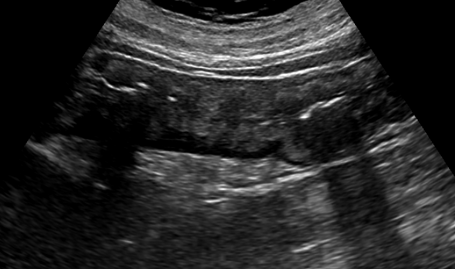

虚血性大腸炎とは何らかの原因で突然、または一過性の血流障害が生じて、大腸の粘膜に十分な血液が行き届かなくなる(虚血状態になる)腸炎を指します。

• 超音波検査